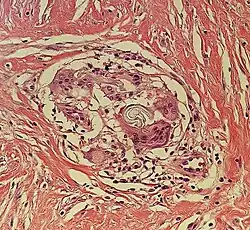

| Kaposi's sarcoma in patch stage | The patch stage typically shows irregular proliferation of jagged vascular channels in the dermis below an integral epidermis. The so-called promontory sign is sometimes found in patch stage lesions and denotes vascular spaces surrounding pre-existing blood (see image).[23]

vessels |

![]() |